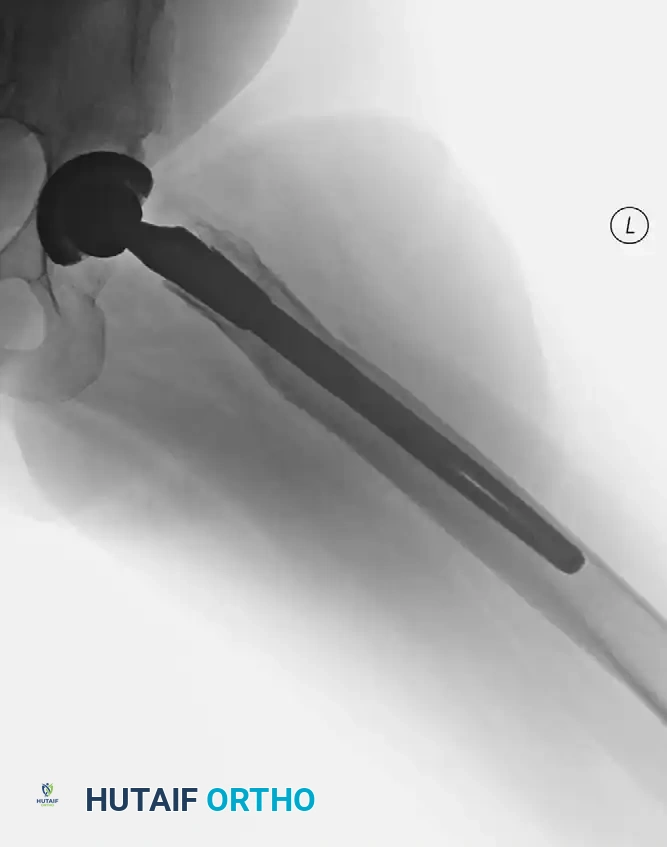

Radiographic Case Examples: Inflammatory Arthropathy and Osteopenia Management

Severe osteopenia and protrusio in a patient with rheumatoid arthritis.

Careful reaming of the soft, osteopenic acetabulum to avoid medial wall blowout.

Use of a multi-hole cup for enhanced screw fixation in poor bone stock.

Preparation of the widened, thin-corticed femoral canal.

Final construct demonstrating stable fixation despite severe osteopenia.

Long-term follow-up showing stable bone ingrowth without progressive radiolucencies.